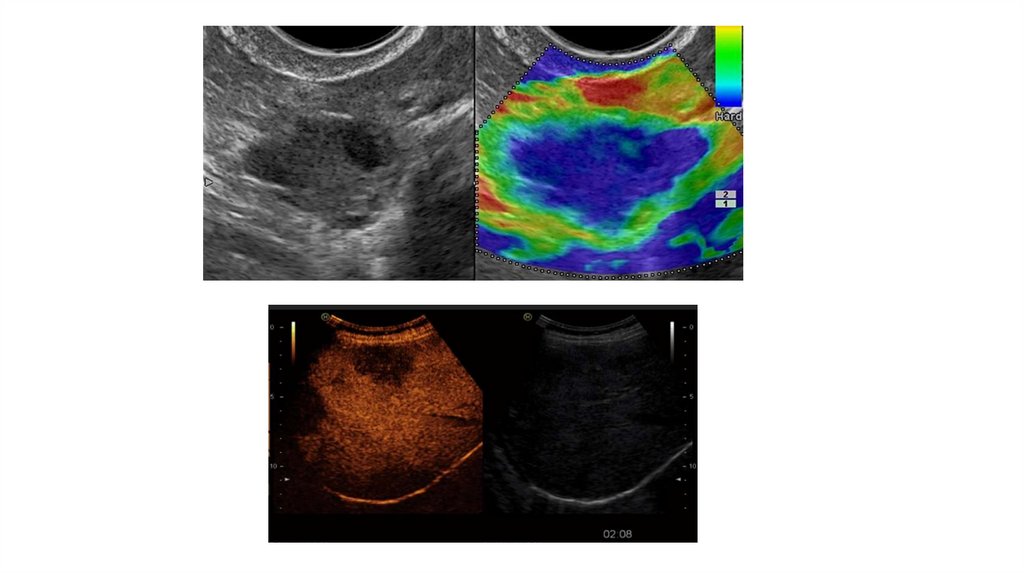

Эластография;

Ультразвуковое исследование с применением контрастирующих

препаратов;

• Мультимодальная визуализация.

Мультимодальная визуализация

Мультимодальная визуализация УЗИ — технология сравнения

ультразвуковых изображений в режиме реального времени с

изображениями, полученными различными методами лучевой

диагностики (КТ, МРТ) на одном экране.